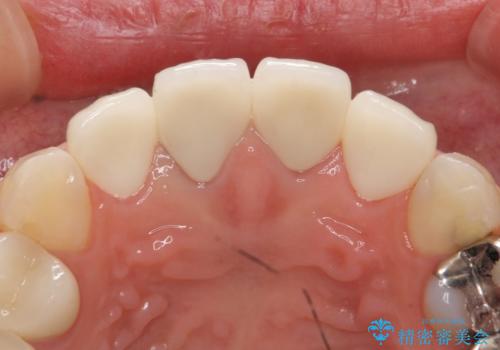

- 上顎の前から2番目の歯の古い樹脂をセラミックにしたいといらっしゃった方の症例です。

古い樹脂を除去後、オールセラミッククラウンによる補綴を行いました。